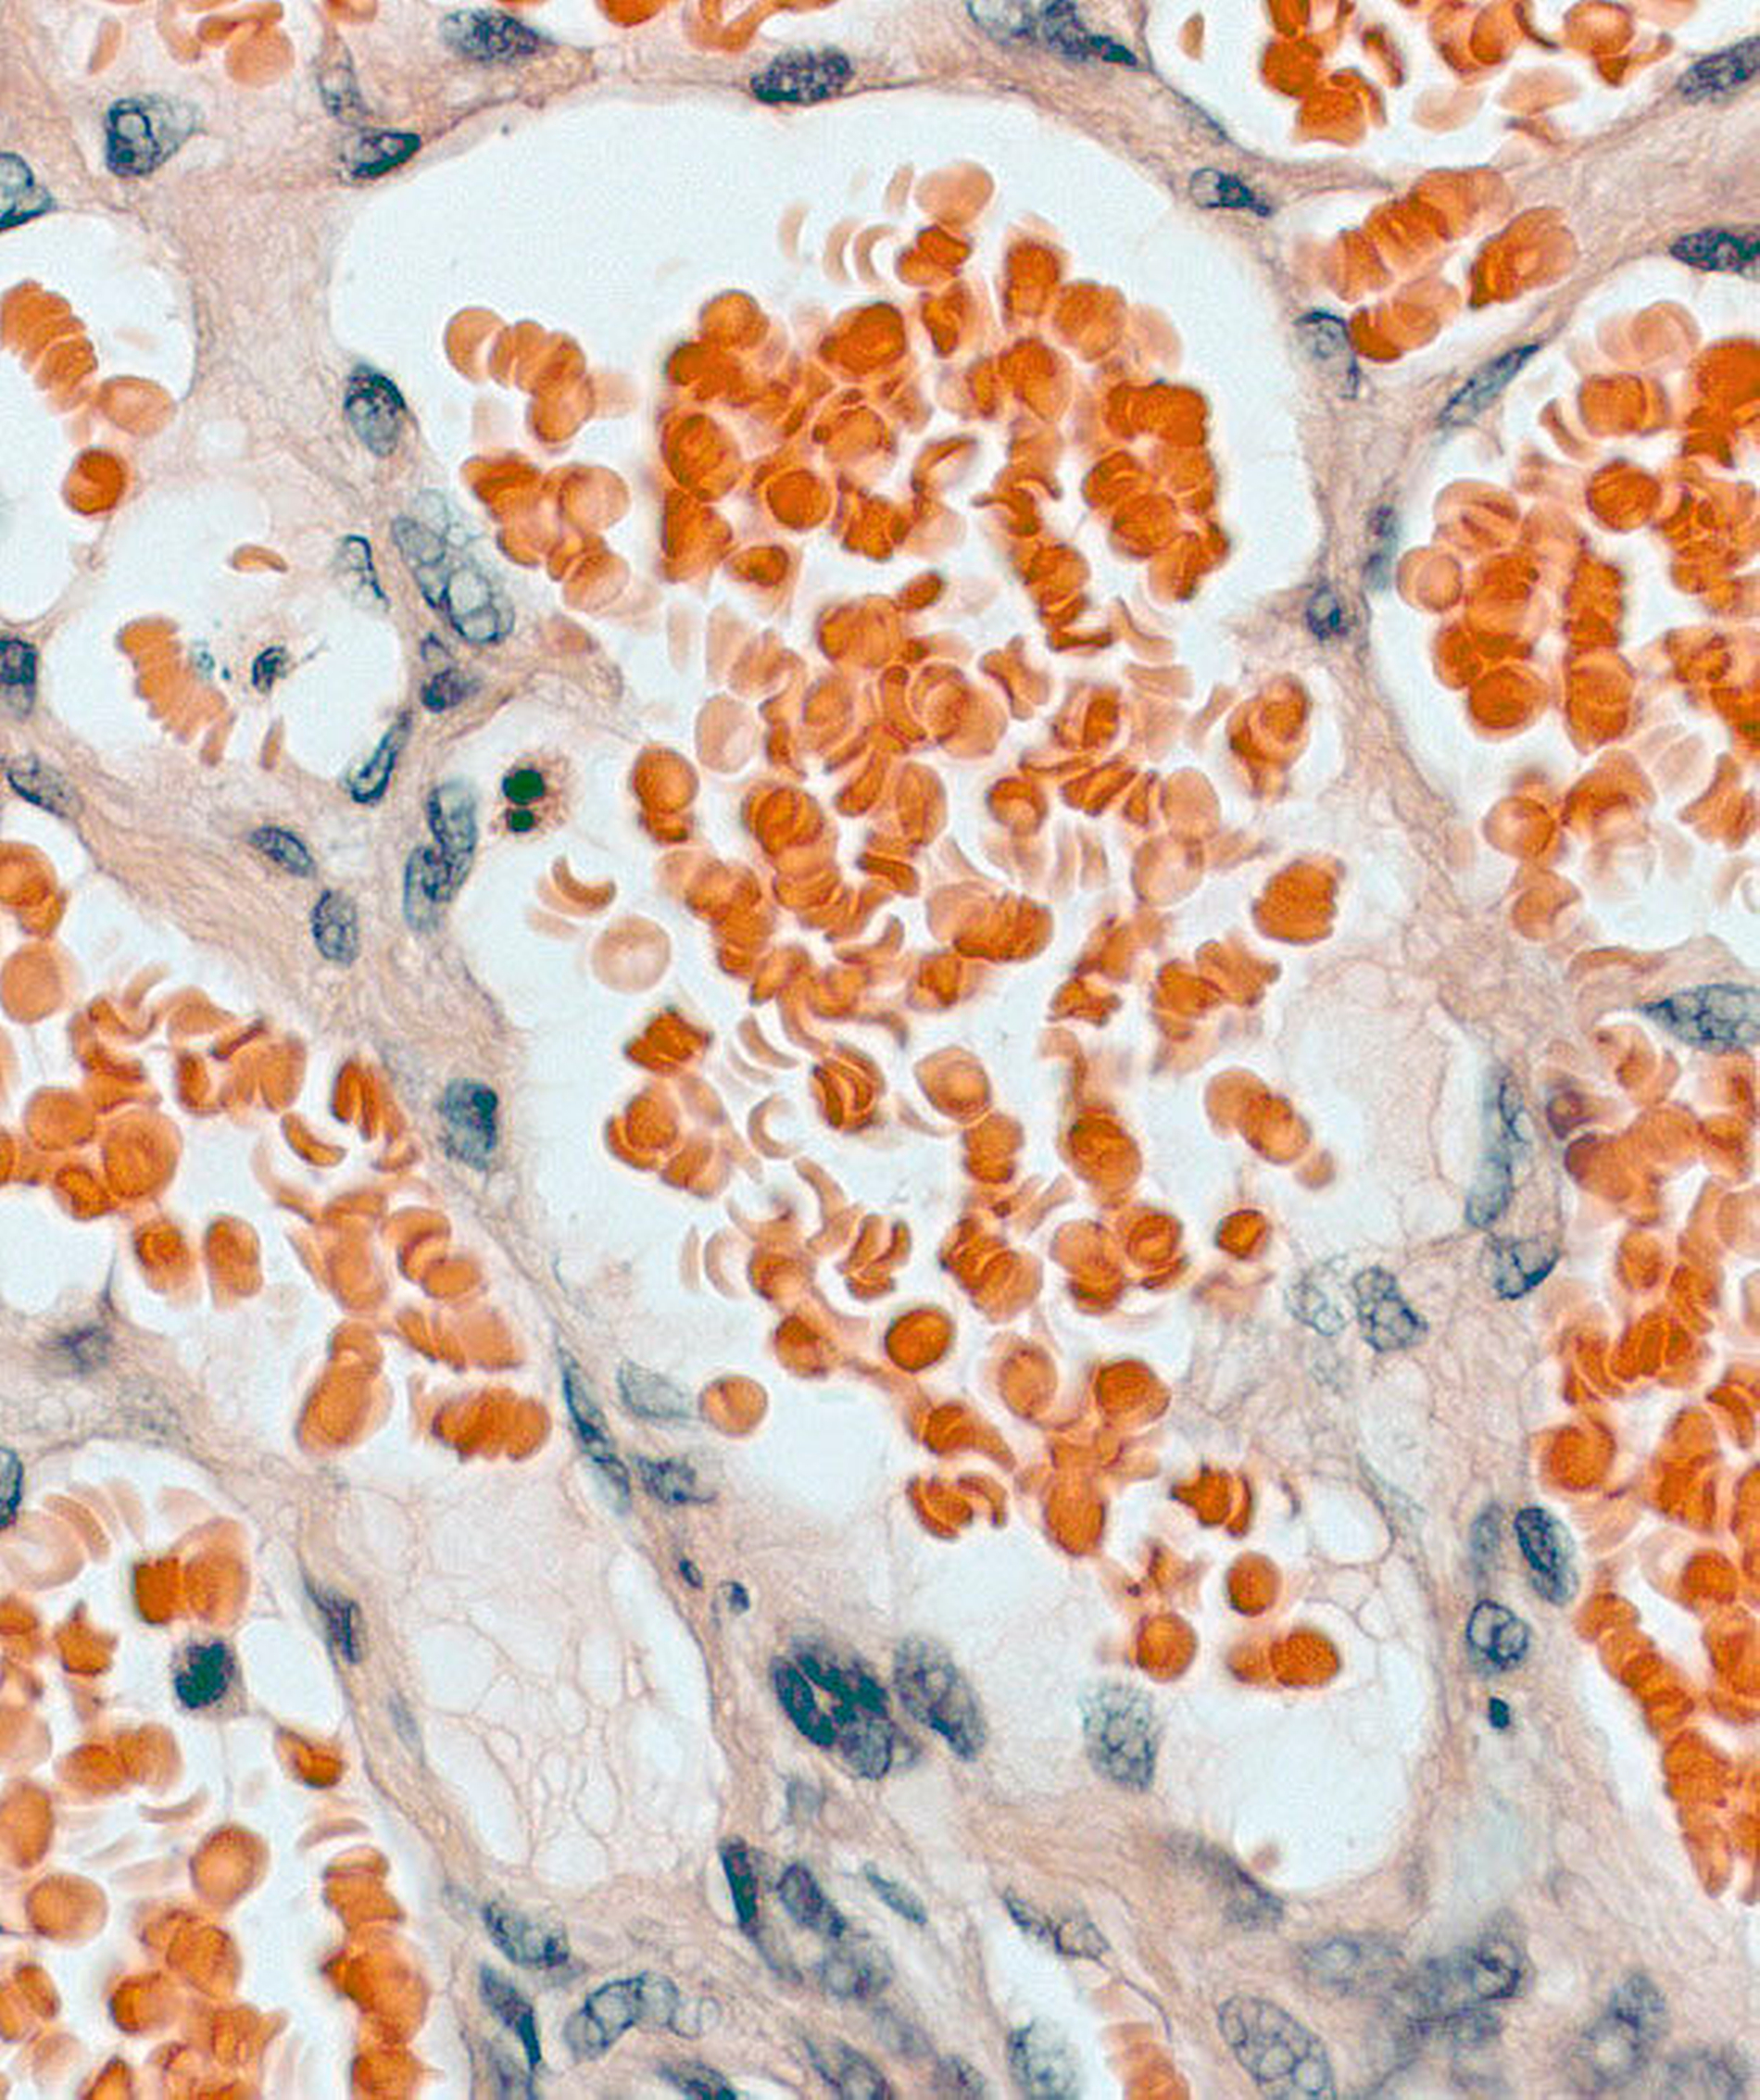

Die histopathologische Untersuchung des entnommenen Gewebes ergab ektatisch erweiterte venöse und wandstärkere arterielle Gefäße im Sinne einer vaskulären Malformation (Abbildung 6). In den Verlaufsuntersuchungen zeigte sich eine komplikationslose Wundheilung ohne Anhalt auf ein Rezidiv.